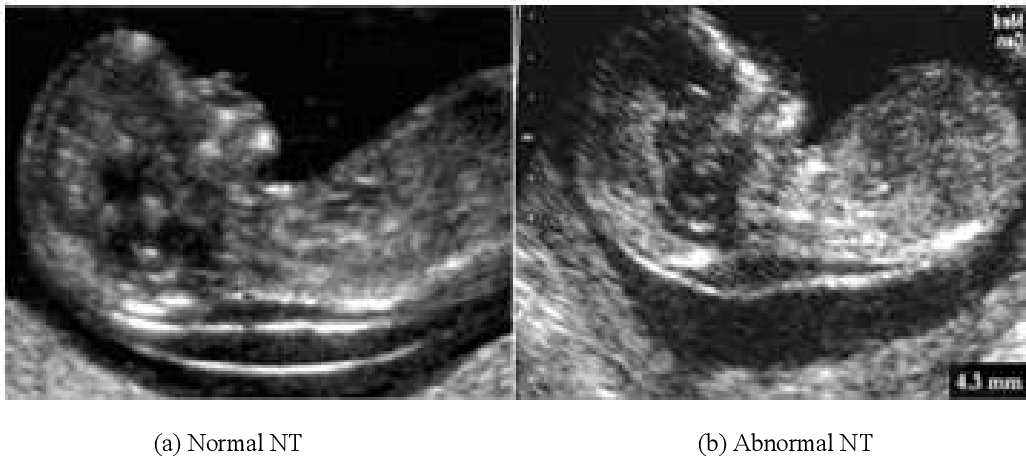

تست اولتراسوند برای شفافیت نوکال جنین (NT)

در این آزمایش از سونوگرافی برای مشاهده پشت گردن نوزاد استفاده می شود. افزایش مایع یا ضخیم شدن پوست را بررسی می کند. اینها ممکن است به معنای نقص باشد.

گردن: اندازه گیری شفافیت نوکال، که تجمع مایع موجود در پشت جنین است. مقادیر بالای شفافیت نوکال با ناهنجاری های ژنتیکی به ویژه سندرم داون مرتبط است.

در این نوع از سونوگرافی، ضخامت مایع پشت گردن جنین NT یا Nuchal Translucencyاندازهگیری خواهد شد. همین طور وجود یا عدم وجود استخوان بینی (Nasal Bone) بررسی میشود. ترکیب نتایج این سونوگرافی با آزمایش خون Free Beta-hCG و PAPP-Aمیتواند تصویری نسبی از سلامت کروموزومی جنین ارائه دهد.

انجام سونوگرافی NT: متخصص سونوگرافی در این مرحله ضخامت پشت گردن جنین را به دقت اندازهگیری کرده و سایر ساختارهای مهم مانند استخوان بینی، مثانه و ضربان قلب را بررسی میکند.